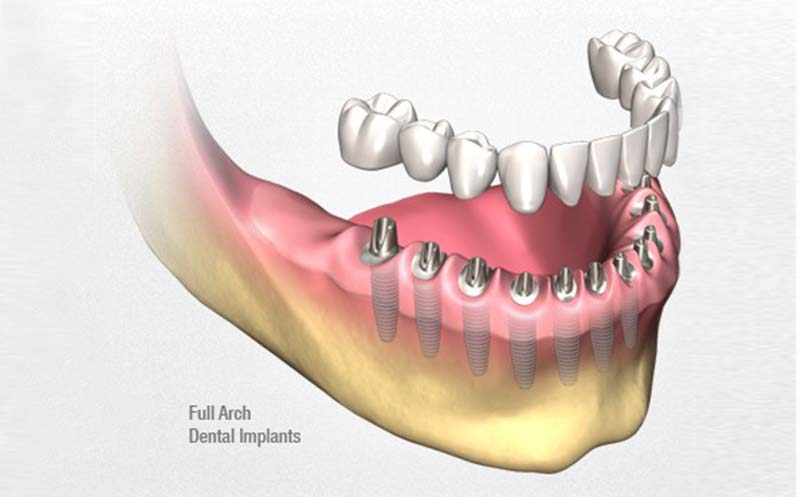

一、All-on-4 全口植牙技術

技術原理

利用四根植體(前2直、後2斜)固定整排假牙,避免補骨,縮短療程。

二、All-on-6 強化型全口重建

在All-on-4基礎上,加裝2根植體,提高支撐力與穩定性。